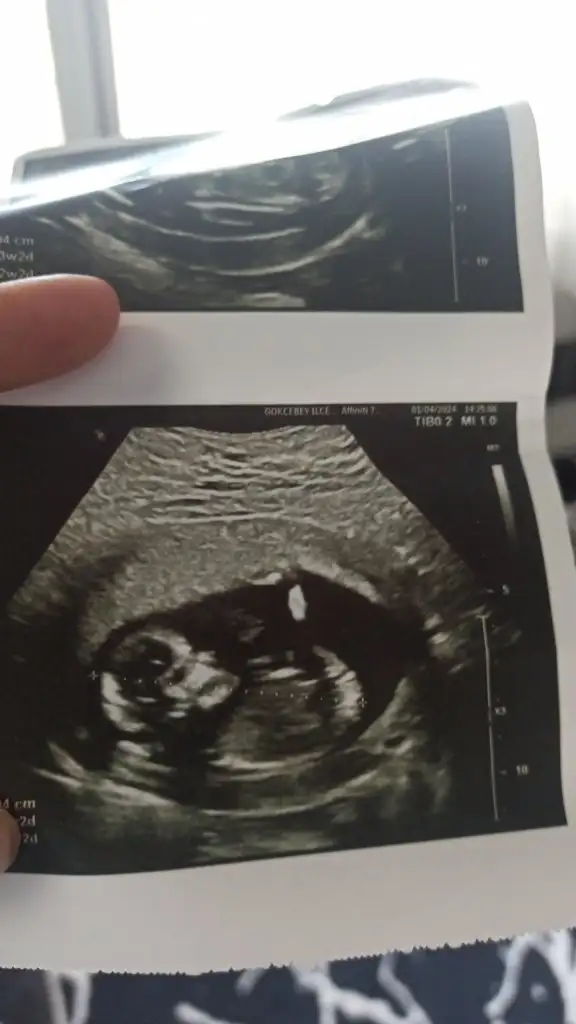

Bizede tahminde bulunur musunuz kızlar

Rica etsem bana da bakar mısınız? Bu resimde 10+1.Kalp atımı 8. Haftada 150 civarıydı en son gittiğimde sormadım şimdiden teşekkürler🫶🏻